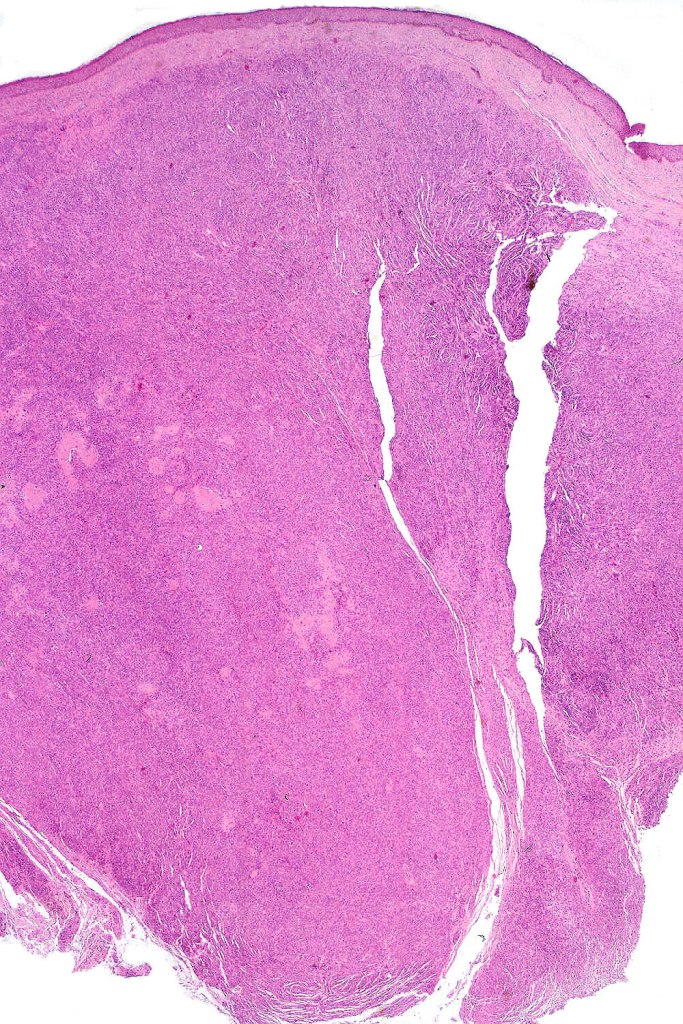

Histological features

•The nodule generally merges with the adjacent nevus but sometimes it can be sharply circumscribed

•It is hypercellular and most often composed of epithelioid cells showing little pleomorphism & only occasional mitoses

•Nuleoli are small

•Intracytoplasmic pseudo-inclusions

•The constituent cells are generally larger than the adjacent nevus cells

•Some examples show more marked pleomorphism with prominent nucleoli and increased mitotic activity but abnormal mitoses are not a feature. These are not associated with any sinister biological potential

•Absence of necrosis, hemorrhage or Pagetoid spread in the overlying epidermis

•Spindle cell, small blue cell, blue nevus-like features, Spitzoid & proliferative nodules with mesenchymal differentiation (myofibroblastic, chondroid & osteoid) can be seen